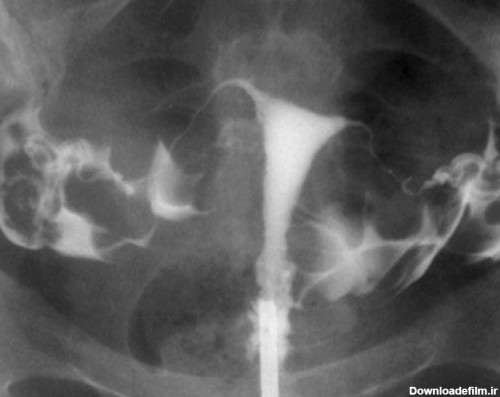

عکس رنگی رحم HSG چیست ؟ - هیستروسالپنگوگرافی یا عکس رنگی رحم یک نوع عکسبرداری با مادۀ حاجب از لگن برای زنان است که عکس رنگی رحم

عکس رنگی رحم یا هیستروسالپنگوگرافی روشی است که به منظور بررسی داخل رحم و لوله های رحمی انجام می گیرد و انجام آن در ارزیابی ناباروری بسیار مهم است.